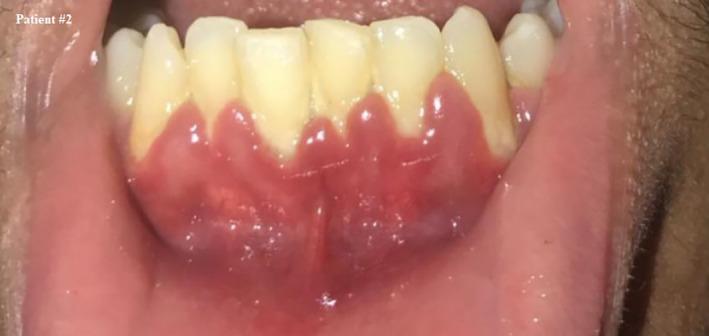

与新冠病毒感染相关的牙龈出血

Gingival bleeding associated with COVID-19 infection.

Gingival bleeding, which was not previously present, may be a preceding symptom associated with COVID-19 infections, preceding or coincidental with fever, other clinical signs, and positive testing.

先前不存在的牙龈出血可能是与新冠病毒感染相关的前驱症状,出现在发热、其他临床症状及检测呈阳性之前或同时出现。